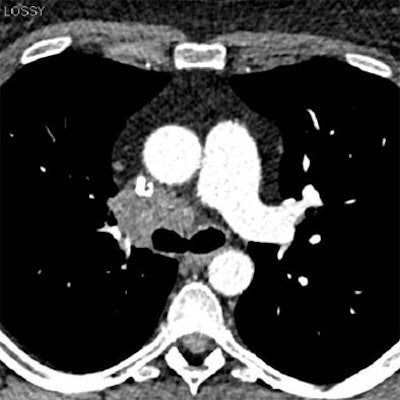

Chest CT exams obtained six months apart in a 40-year-old, obese woman (BMI: 36.5 kg/m2) referred for follow-up of thoracic malignancy. First scan performed with standard dose obtained at the level of the left pulmonary artery, and reconstructed using standard FBP (120 kVp DLP = 326 mGy.cm, Noise = 19.8 HU, and CNR = 8.1) delivers higher noise and radiation dose than low-dose SAFIRE reconstructed image from the same patient six months later, below (100 kVp DLP = 143 mGy.cm, Noise = 17.1 HU, and CNR = 9.2). Despite the dose reduction in the follow-up image, objective image noise measured at the level of the trachea was slightly reduced, and the contrast-to-noise ratio was slightly improved. Images courtesy of Dr. Julien Pagniez and Dr. Martine Rémy-Jardin.